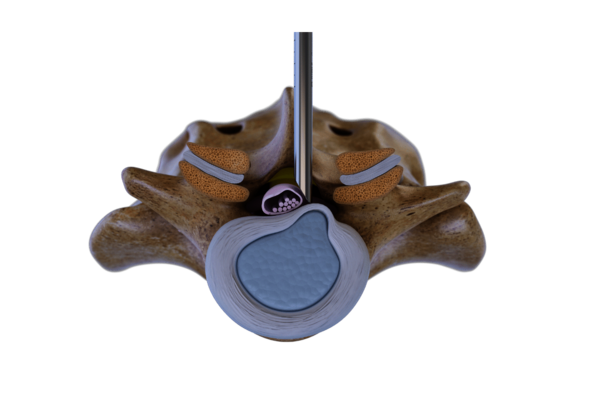

Das VERTEBRIS lumbar Instrumentenset ist für die vollendoskopische Dekompression der Lenden- und Brustwirbelsäule konzipiert. Zu den Indikationen gehören Bandscheibenvorfälle, Wirbelsäulenzysten und Spinalkanalstenosen. Die Eingriffe können über transforaminale, extraforaminale oder interlaminäre Zugänge durchgeführt werden.

Diese Technik nutzt das Foramen intervertebrale als Zugang zur Pathologie. Der Zugang wird unter Röntgenkontrolle mit einer Punktionskanüle geführt, gefolgt von der Dilatation und dem Einführen der Arbeitshülse.

Der Eingriff erfolgt unter kontinuierlicher Spülung mit hochauflösender endoskopischer Bildgebung. Spezialisierte Instrumente wie Zangen, Fräser und Stanzen gewährleisten einen effektiven und präzisen Eingriff.

Der Zugang zum Wirbelsäulenkanal erfolgt durch das hintere interlaminäre Fenster. Ein Dilatator wird ohne vorherige Punktion zum Ligamentum flavum geführt. Anschließend wird die Arbeitshülse platziert, so dass der Eingriff mit einem hochauflösenden Diskoskop unter kontinuierlicher Spülung durchgeführt werden kann.

Die Komponenten des Systems sind optimiert, um das Trauma zu minimieren und die chirurgische Präzision zu erhöhen. Bandscheibenvorfälle und stenotische Knochenanteile können unter vollendoskopischer Sicht effektiv reseziert werden.